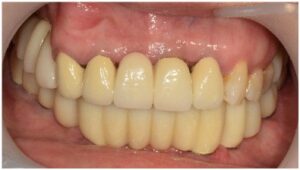

최종 보철물은

자연치아와 강도가 유사하고

심미적인 지르코니아 보철물로

마무리해 드렸습니다.

모든 치료가 마무리된

파노라마 사진과

구강 내 사진인데요.

환자분께서는

치료 후 양측 저작이 편안해지고

심미적으로 변한 모습에

만족해하셨습니다.

전 > 후